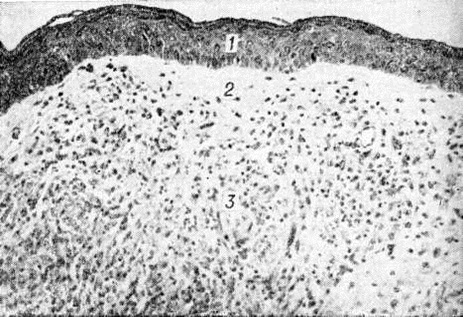

Гистологический исследование биопсийного материала имеет важное значение для установления диагноза и прогноза болезни. Биопсии подвергаются участки поражённой кожи, изредка — поверхностно расположенные нервы. Морфологически изменения при Лепра проявляются в виде гранулем двух полярных типов — лепроматозного (LL) и туберкулоидного (ТТ), а также трёх групп — погранично-туберкулоидной (ВТ), пограничной (ВВ) и погранично-лепроматозной (BL).

Гистологически лепроматозный тип характеризуется лепроматозной гранулемой кожи, которая представляет инфильтрат, расположенный в сетчатом слое, отделённый от эпидермиса непоражённой зоной коллагеновой ткани. Основными клеточными элементами лепроматозной гранулемы являются лепрозные клетки; кроме того, наблюдаются отдельные плазматические, лимфоидные клетки, единичные фибробласты, многоядерные пенистые клетки (цветной рисунок 1—6). Лепрозные клетки относятся к макрофагам, характеризуются бледным ядром и «пенистой» цитоплазмой (рисунок 5) за счёт содержания липидов. Лепрозный макрофаг на ранних стадиях содержит жирные кислоты, фосфолипиды, ненасыщенные липиды; на стадии развития процесса преобладают нейтральные жиры и кислотные липиды. Большинство исследователей считает, что основная масса липидов представляет собой продукт метаболизма и распада микобактерий Лепра. Наиболее характерная особенность лепрозного макрофага — нахождение и размножение в нем большого количества микобактерий Лепра, то есть явление незавершённого фагоцитоза (смотри полный свод знаний). В цитоплазме лепрозной клетки выявляется высокий уровень окислительно-восстановительных ферментов, кислой фосфатазы, неспецифической эстеразы и не обнаруживается активность липазы. Для гистологический картины LL характерно также наличие капилляров со значительным сужением их просвета за счёт пролиферации и набухания эндотелиальных клеток, содержащих большое количество микобактерий типа «глоби». Кожные нервы пронизаны инфильтратами из микробосодержащих клеток (цветной рисунок 7 и 10). Микобактерии обнаруживаются также в клетках эндоневрия. В лепроматозных поражениях большой давности отмечается частичное или полное разрушение придатков кожи (фолликулов волос, сальных и потовых желёз).

При туберкулоидном типе патологический процесса сформировавшийся инфильтрат может быть массивным, занимающим все слои собственно кожи, или располагаться отдельными очагами. Характерно разрушение субэпидермального слоя коллагеновой ткани с расположением гранулемы непосредственно под эпидермисом с эрозированием последнего. Основную массу гранулемы составляют эпителиоидные клетки (смотри полный свод знаний), расположенные в центре и окружённые по периферии валом из лимфоидных клеток (смотри полный свод знаний Лимфоциты), встречаются гигантские многоядерные клетки типа Лангханса (смотри полный свод знаний Гигантские клетки), в небольшом количестве обнаруживаются плазматические клетки (смотри полный свод знаний), тучные клетки (смотри полный свод знаний), фибробласты. В период обострения в гранулеме наблюдается обилие полиморфно-ядерных лейкоцитов (смотри полный свод знаний). Клеточные элементы не содержат микобактерий и липидов. Характерно утолщение нервных стволов за счёт массивной инфильтрации эпителиоидными клетками.

Морфологически структуры, содержащие элементы, характерные для обоих типов Лепра и являющиеся как бы переходной стадией между полярными типами, характерны для пограничной Лепра При недифференцированной Лепра наблюдается картина банального хронический воспаления (смотри полный свод знаний) без специфических изменений. Основными гистологический критериями, определяющими принадлежность к классификационным группам Ридли — Джоплинга, являются следующие морфологический особенности инфильтрата. 1. Клеточный состав гранулемы. В верхней половине спектра (ТТ, ВТ и ВВ) характерно наличие эпителиоидных клеток (цветной рисунок 8) и для ТТ — многоядерных (гигантских) клеток типа Лангханса (цветной рисунок 9). При ВВ эпителиоидные клетки часто отделены друг от друга отёком. В нижней части спектра (BL и LL) эпителиоидные клетки уступают место макрофагам, цитоплазма которых по мере приближения к типу LL становится более плотной, пенистой и содержит жир. 2. Плотность популяций микобактерий. Количество микобактерий возрастает пропорционально от верхней части спектра к нижней. В числовом выражении показатель бактериальной насыщенности лепроматозного инфильтрата для ТТ, ВТ, ВВ, BL и LL составляет 0/1; 0/2,5; 3/4,5; 4/5,5; 5/6,5 соответственно. 3. Количество и топография лимфоцитов в гранулеме. Для ТТ и ВТ свойственно высокое содержание лимфоцитов, расположенных в виде плотного бордюра вокруг массы эпителиоидных клеток. При ВВ и LL количество лимфоцитов чаще снижено, они рассеяны по гранулеме и не образуют вала. 4. Поражение кожных нервов. Для туберкулоидной части спектра характерно значительное утолщение нерва за счёт массивного инфильтрата (повышение максимального диаметра пучка при ТТ). Для ВВ и BL патогномоничны изменения периневрия в виде луковичной кожуры (onion skin) за счёт расслоения его инфильтратом из лимфоцитов, плазмоцитов (при В В) или бактериосодержащих макрофагов (при BL). 5. Отношение к эпидермису. При ТТ и ВТ гранулема располагается непосредственно под эпидермисом и может эрозировать его. При ВВ, BL и LL между инфильтратом и эпидермисом постоянно остаётся непоражённая зона толщиной 30 — 75 микрометров — так называемый слой Ипа, состоящий из коллагеновой ткани.